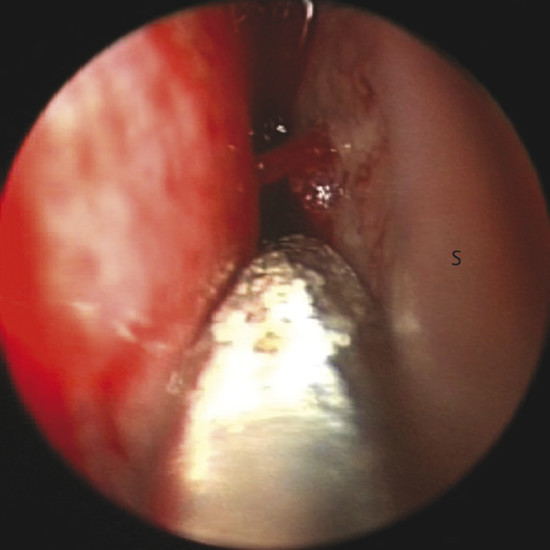

Bleeding can be seen originating from a septal branch of the AEA, showing a close anatomic relation with the axilla of the middle turbinate (Fig. 13‑4). It is extremely important to consider this anatomical relation during harvesting the flap.